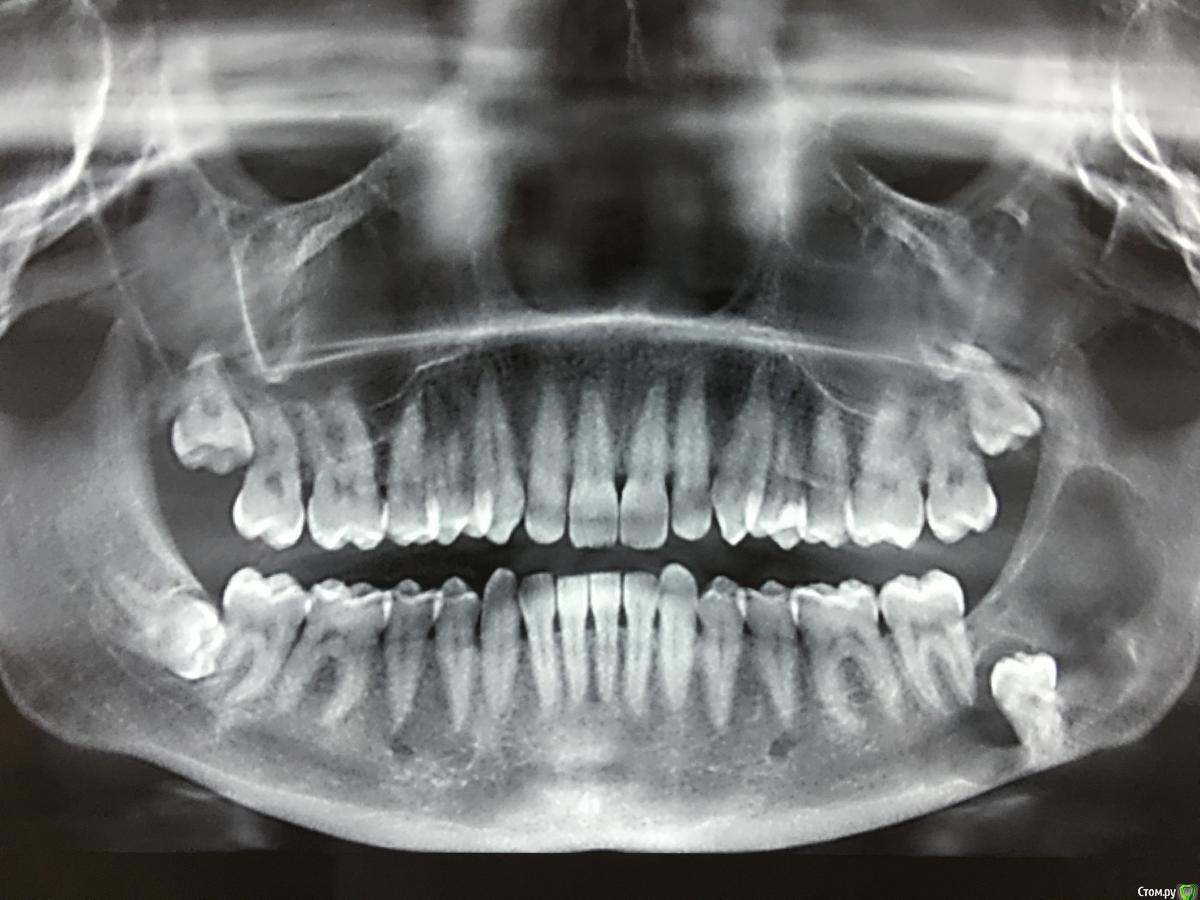

Jurai Опубликовано 14 апреля, 2017 Поделиться Опубликовано 14 апреля, 2017 Сегодняшний улов, все из одного пациента. На удивление быстро. Приятно было работать. 6 Ссылка на комментарий

vse32 Опубликовано 14 апреля, 2017 Поделиться Опубликовано 14 апреля, 2017 Это все восьмерки? Я с разных сторон в один раз стараюсь не удалять, оставляю одну сторону для жевания. Но зубки зачетные, все один к одному, как близнецы. Хорошая работа. 1 Ссылка на комментарий

___49___ Опубликовано 15 апреля, 2017 Поделиться Опубликовано 15 апреля, 2017 (изменено) Это все восьмерки? Я с разных сторон в один раз стараюсь не удалять, оставляю одну сторону для жевания. Но зубки зачетные, все один к одному, как близнецы. Хорошая работа.Тоже так делаю , делю на лево и право( но это больше из-за менталитета контигента с которым работаю). Юрай скорее всего поушивала все, и работала с премедикацией .Для печени гуд 1 курс медикаментов на все 4 зуба мудрости. Изменено 15 апреля, 2017 пользователем ___49___ Ссылка на комментарий

Jurai Опубликовано 15 апреля, 2017 Поделиться Опубликовано 15 апреля, 2017 Все восьмерки, 18, 28, 48. Везде ПРФ и швы, и прекрасно. На все полторы карпулы ультракаина ДС ушло. 2 Ссылка на комментарий